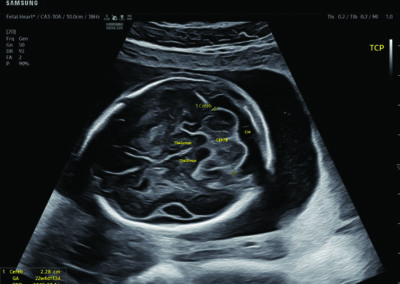

Procedural Services

Comprehensive, advanced and expert MFM care for high-risk pregnancies

- Neural tube defects